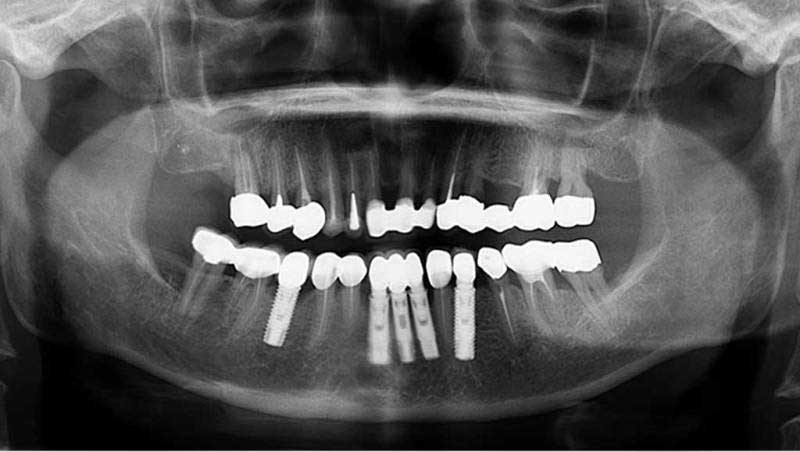

植牙併發症處理

影響植體使用年限最大的併發症當屬細菌感染了,陳先生50多歲,10多年來深受牙周病所苦,每年總有數次牙齦腫脹,吃東西很不方便,控制好牙周病後,缺牙區以植體修復,努力執行正確的口腔清潔,每年定期回診洗牙,瀕臨拔牙的重度牙周病牙齒都相安無事。但退休後不在台南工作,家住鄉下,牙間刷用完後也沒再購買,快2年沒有回診,直到牙齦再度腫起來。這回一顆牙周病牙需拔除,一顆受感染的植體需手術清創,相當懊悔不該鬆懈,沒有做好保養的工作。

植體是鈦金屬,所以並不會蛀牙,但並非一勞永逸,因它沒有牙周韌帶,牙齦和植體的連結比自然牙弱,細菌的侵犯常會限制在自然牙的牙齦區,但在植體則很快就侵犯到牙骨,引起骨頭破壞,如及早發現治療可重新恢復健康,放任不管將危及它的長遠性。

植牙併發症處理案例

案例1

植牙併發症處理前

植牙併發症處理中

植牙併發症處理後

案例2